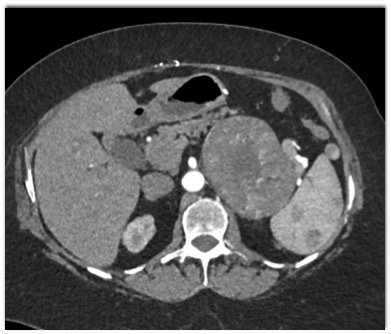

The most likely diagnosis in this case is?

adrenal carcinoma

adrenal lymphoma

pheochromocytoma

adrenal hemorrhage